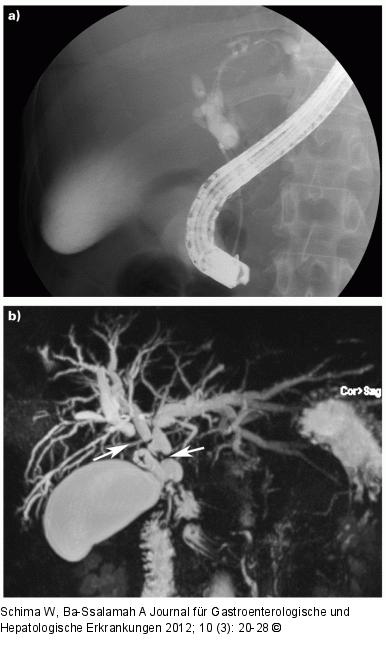

Abbildung 4a-b: Cholangitis Primär sklerosierende Cholangitis im fortgeschrittenen Stadium. (a) Die ERCP kann lediglich die distale Striktur darstellen, nicht jedoch die intrahepatischen Gallenwege. (b) Die MRCP zeigt die ausgeprägten Strikturen intra- und extrahepatisch (Pfeile) mit deutlicher Cholangiektasie. |